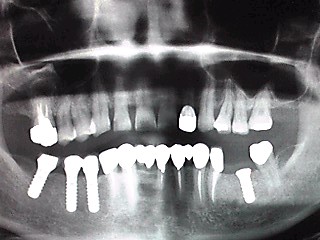

以前、入れ歯の説明をお届けしたと思います。

ハトャのじぃとばぁも入れ歯です。

堅いもの、つまみや漬け物などを好むので歯は年齢の割に祖父達はしっかりしている気がしますネ、はぃ。。総(全部)ではなく、本当に一部分ですね、ハィ。